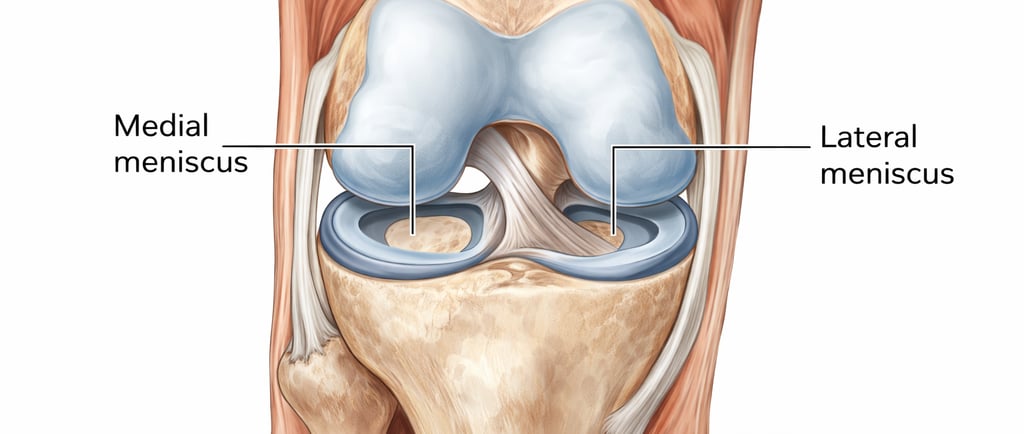

Qu’est-ce que le ménisque du genou

Le genou contient deux ménisques :

le ménisque interne

le ménisque externe

Ces structures cartilagineuses ont plusieurs rôles :

absorber les chocs

stabiliser l’articulation

répartir les charges

protéger le cartilage

Une atteinte du ménisque peut perturber le bon fonctionnement du genou.